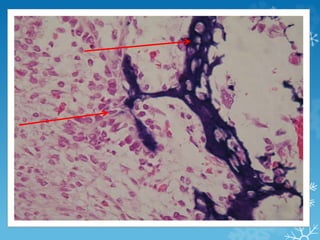

Este documento describe el desarrollo del sistema esquelético y óseo en el cuerpo humano. Se forma a partir del mesodermo paraxial en la tercera semana de desarrollo, cuando se forman los somitas que dan origen a las vertebras, costillas, y otros huesos. En la cuarta semana, el mesénquima derivado del mesodermo se transforma y comienzan a verse los esbozos de las extremidades. Existen dos procesos de osificación - intramembranosa, donde las células forman directamente hueso, y endocondral